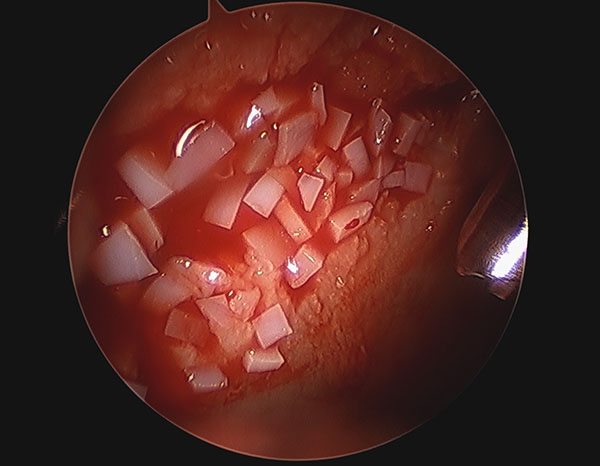

The allograft procedure uses particles of natural cartilage with living cells packed in a small, sealed container. Unlike other repairs, it uses no water, which would wash the cells away, Pascual-Garrido said. Guided by arthroscopic imagery, she uses a catheter-like delivery device and miniature instruments to put fibrin glue in the lesion, followed by the cartilage cells, and then another layer of the glue to fix the cells in place “like a sandwich.” With time, new cartilage begins to grow.